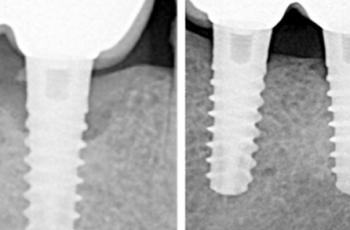

Tratamiento no quirúrgico de la periimplantitis. A propósito de un caso... Cirugía periodontal y periimplantaria | UIC Tratamiento no quirúrgico de la periimplantitis. A propósito de un caso... Se presenta el caso de una paciente de 58 años de edad, sin antecedentes médicos de interés y no fumadora. El motivo... Etiología, diagnóstico y tratamiento de la periimplantitis: Caso... Tto. Periimplantario | UV Etiología, diagnóstico y tratamiento de la periimplantitis: Caso... Presentamos nuevo caso clínico realizado por los doctores Manuel Rodríguez Aranda, Francisco... Efectividad del Tratamiento en Periodontitis Agresiva Tto. Periodontal | UIC Efectividad del Tratamiento en Periodontitis Agresiva El mantenimiento de la dentición natural en estado de salud ha sido un objetivo importante en... Injerto gingival libre alrededor de implantes dentales. A propósito de un... Cirugía periodontal y periimplantaria | UIC Injerto gingival libre alrededor de implantes dentales. A propósito de un... La cirugía mucogingival reconstructiva alrededor de implantes corrige los defectos de la... Terapia mucogingival en implantes: corrección de las secuelas mucosas de... Cirugía periodontal y periimplantaria | UV Terapia mucogingival en implantes: corrección de las secuelas mucosas de... El caso que se presenta a continuación muestra una resolución impecable de un defecto mucogingival... Importancia del mantenimiento en la evolución de un paciente con... Mantenimiento | UV Importancia del mantenimiento en la evolución de un paciente con... La periodontitis agresiva se define como una enfermedad de rápida progresión en la destrucción... Tratamiento de Recesiones Gingivales Clase III de Miller mediante técnica... Cirugía periodontal y periimplantaria | UIC Tratamiento de Recesiones Gingivales Clase III de Miller mediante técnica... El caso clínico que presentamos a continuación es el de una paciente que acude a la consulta... Tratamiento de un paciente con periodontitis crónica moderada generalizada Tto. Periodontal | UIC Tratamiento de un paciente con periodontitis crónica moderada generalizada El caso clínico que se presenta a continuación, muestra el tratamiento de una paciente...